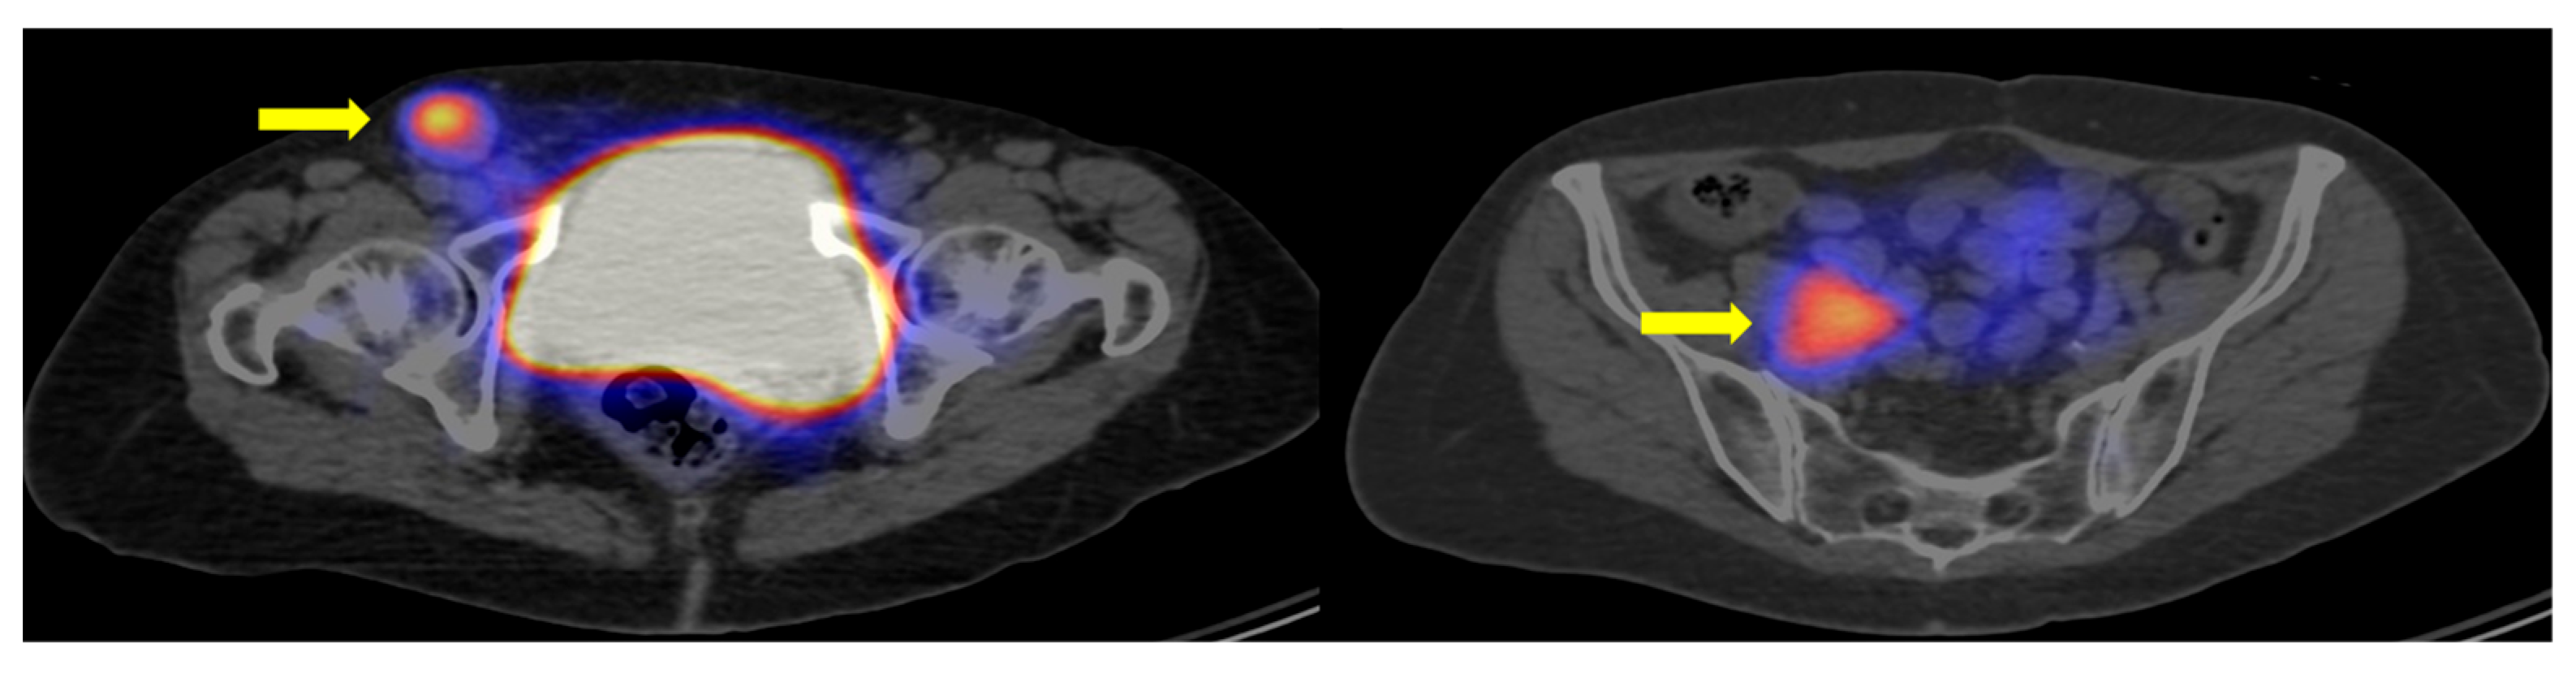

2.3. Image Analysis and Lesion Detection

3.1. Metastatic Neuroendocrine Neoplasms Frequently Exhibit PRRT-Suitable Lesions